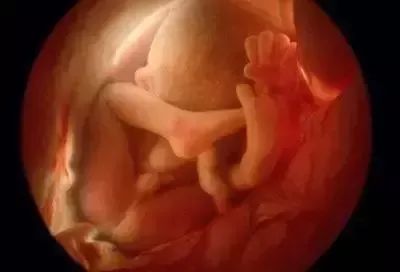

胎儿生长在子宫内,胎儿膜充满羊水。胎儿脐带由脐带与胎盘相连。胎儿生长所需的营养是通过胎盘从母亲身上获取的。

三个月:胎儿的身体为7-9厘米,重约20克,与4-7周相比,胎儿增加了3.4倍以上,躯干和腿部全部发育,头部明显较大,下颚和颊部发达,更重要的是鼻子、嘴唇、根。声带已经长了,脸部更像脸部,眼睛已经被比较了。眼睑生长。它能对外界刺激作出反应。如果你用手戳你的胃,它甚至会移动,但在几周内,你就感觉不到他的活动。胎儿肠生长很快,其中一些进入脐带。他们开始转移到腹腔。胎儿的肾脏分泌尿液进入膀胱。